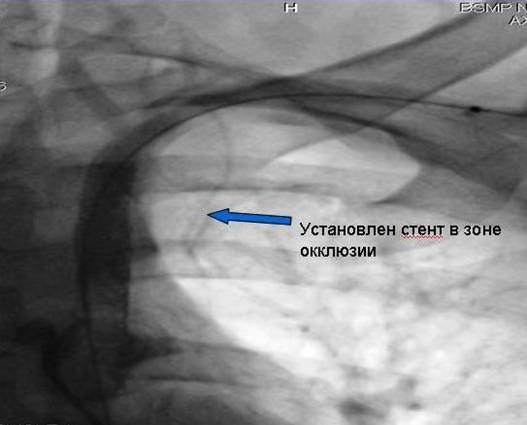

Установление балонорасширяемого стента в зоне

Окклюзии ( т.е. непроходимости сосуда).